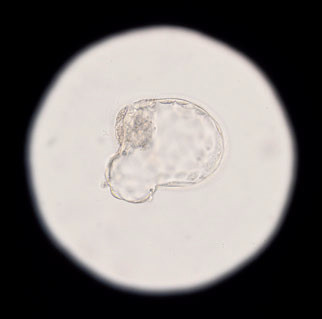

Методы ВРТ — это все научные достижения, процедуры и манипуляции, которые могут применяться, чтобы помочь бесплодным супругам стать счастливыми родителями. Помимо классического ЭКО, к ним относятся ИКСИ (прицельное введение специально отобранного сперматозоида прямо в яйцеклетку), преимплантационное генетическое тестирование (ПГТ), вспомогательный хетчинг и еще много методов, делающих возможным наступление беременности.

Программы ВРТ — скорее юридические понятия. Иногда программа включает в себя сразу несколько методов, но носит название лишь одного из них — и это создает путаницу. Например, программа ЭКО предусматривает как минимум стимуляцию овуляции, пункцию фолликулов, собственно ЭКО, перенос эмбрионов в полость матки, поддержку лютеиновой фазы для сохранения беременности.